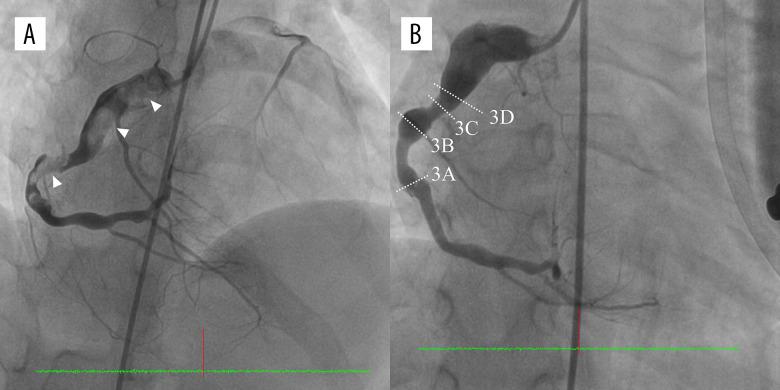

一名 9 岁男孩在 6 岁时被诊断为 KD。由于直径为 8.8 毫米的巨大冠状动脉瘤(CAA)的冠状动脉后遗症,他被开处阿司匹林和华法林。9 岁时,他因急性胸痛就诊于急诊。心电图显示不完全性右束支传导阻滞和右、下导联 ST-T 改变。肌钙蛋白 I 升高。冠状动脉造影发现右 CAA 急性血栓性闭塞。我们进行了抽吸血栓切除术联合静脉注射替罗非班。随后的冠状动脉造影和光学相干断层扫描(OCT)图像发现了白色血栓、钙化、中膜层破坏、内膜不规则增厚和不均匀的内膜边缘。我们开处了抗血小板治疗和华法林,在 3 年的随访中,他恢复良好。

OCT 是一种很有前途的方法,可以影响冠状动脉疾病患者的临床治疗。本报告介绍了伴有巨大 CAA 和急性心肌梗死的 KD 的治疗管理和 OCT 图像。我们使用抽吸血栓切除术联合药物治疗作为初始干预策略。随后的 OCT 图像显示血管壁异常,有助于确定未来的风险和决定进一步的冠状动脉介入和药物治疗。